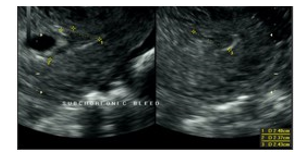

The patient’s post-operative course was unremarkable. She received 1 unit of PRBCs post operatively. An official obstetrical ultrasound was performed on post-operative day (POD) #0 re-confirming the presence of a viable IUP, dated 6.1 weeks with a 2.4 cm sub chorionic bleed (Fig 5-6). The patient was discharged on POD#1. She went on to have a full term spontaneous vaginal delivery of the remaining IUP. Of note, upon chart review, it was noted that the patient was diagnosed with 2 separate episodes of gonorrhea and chlamydia, 6 and 11 years prior, respectively. Both infections had been treated and followed by a negative test of cure. The patient, upon the initial encounter in the ED, did not report this information. Due to the urgent nature of her presentation, she was not immediately assigned to her electronic medical chart, but instead received a temporary chart to allow for her immediate management.

Figure 6: ultrasound imaging of 2.4cm sub-chorionic bleed